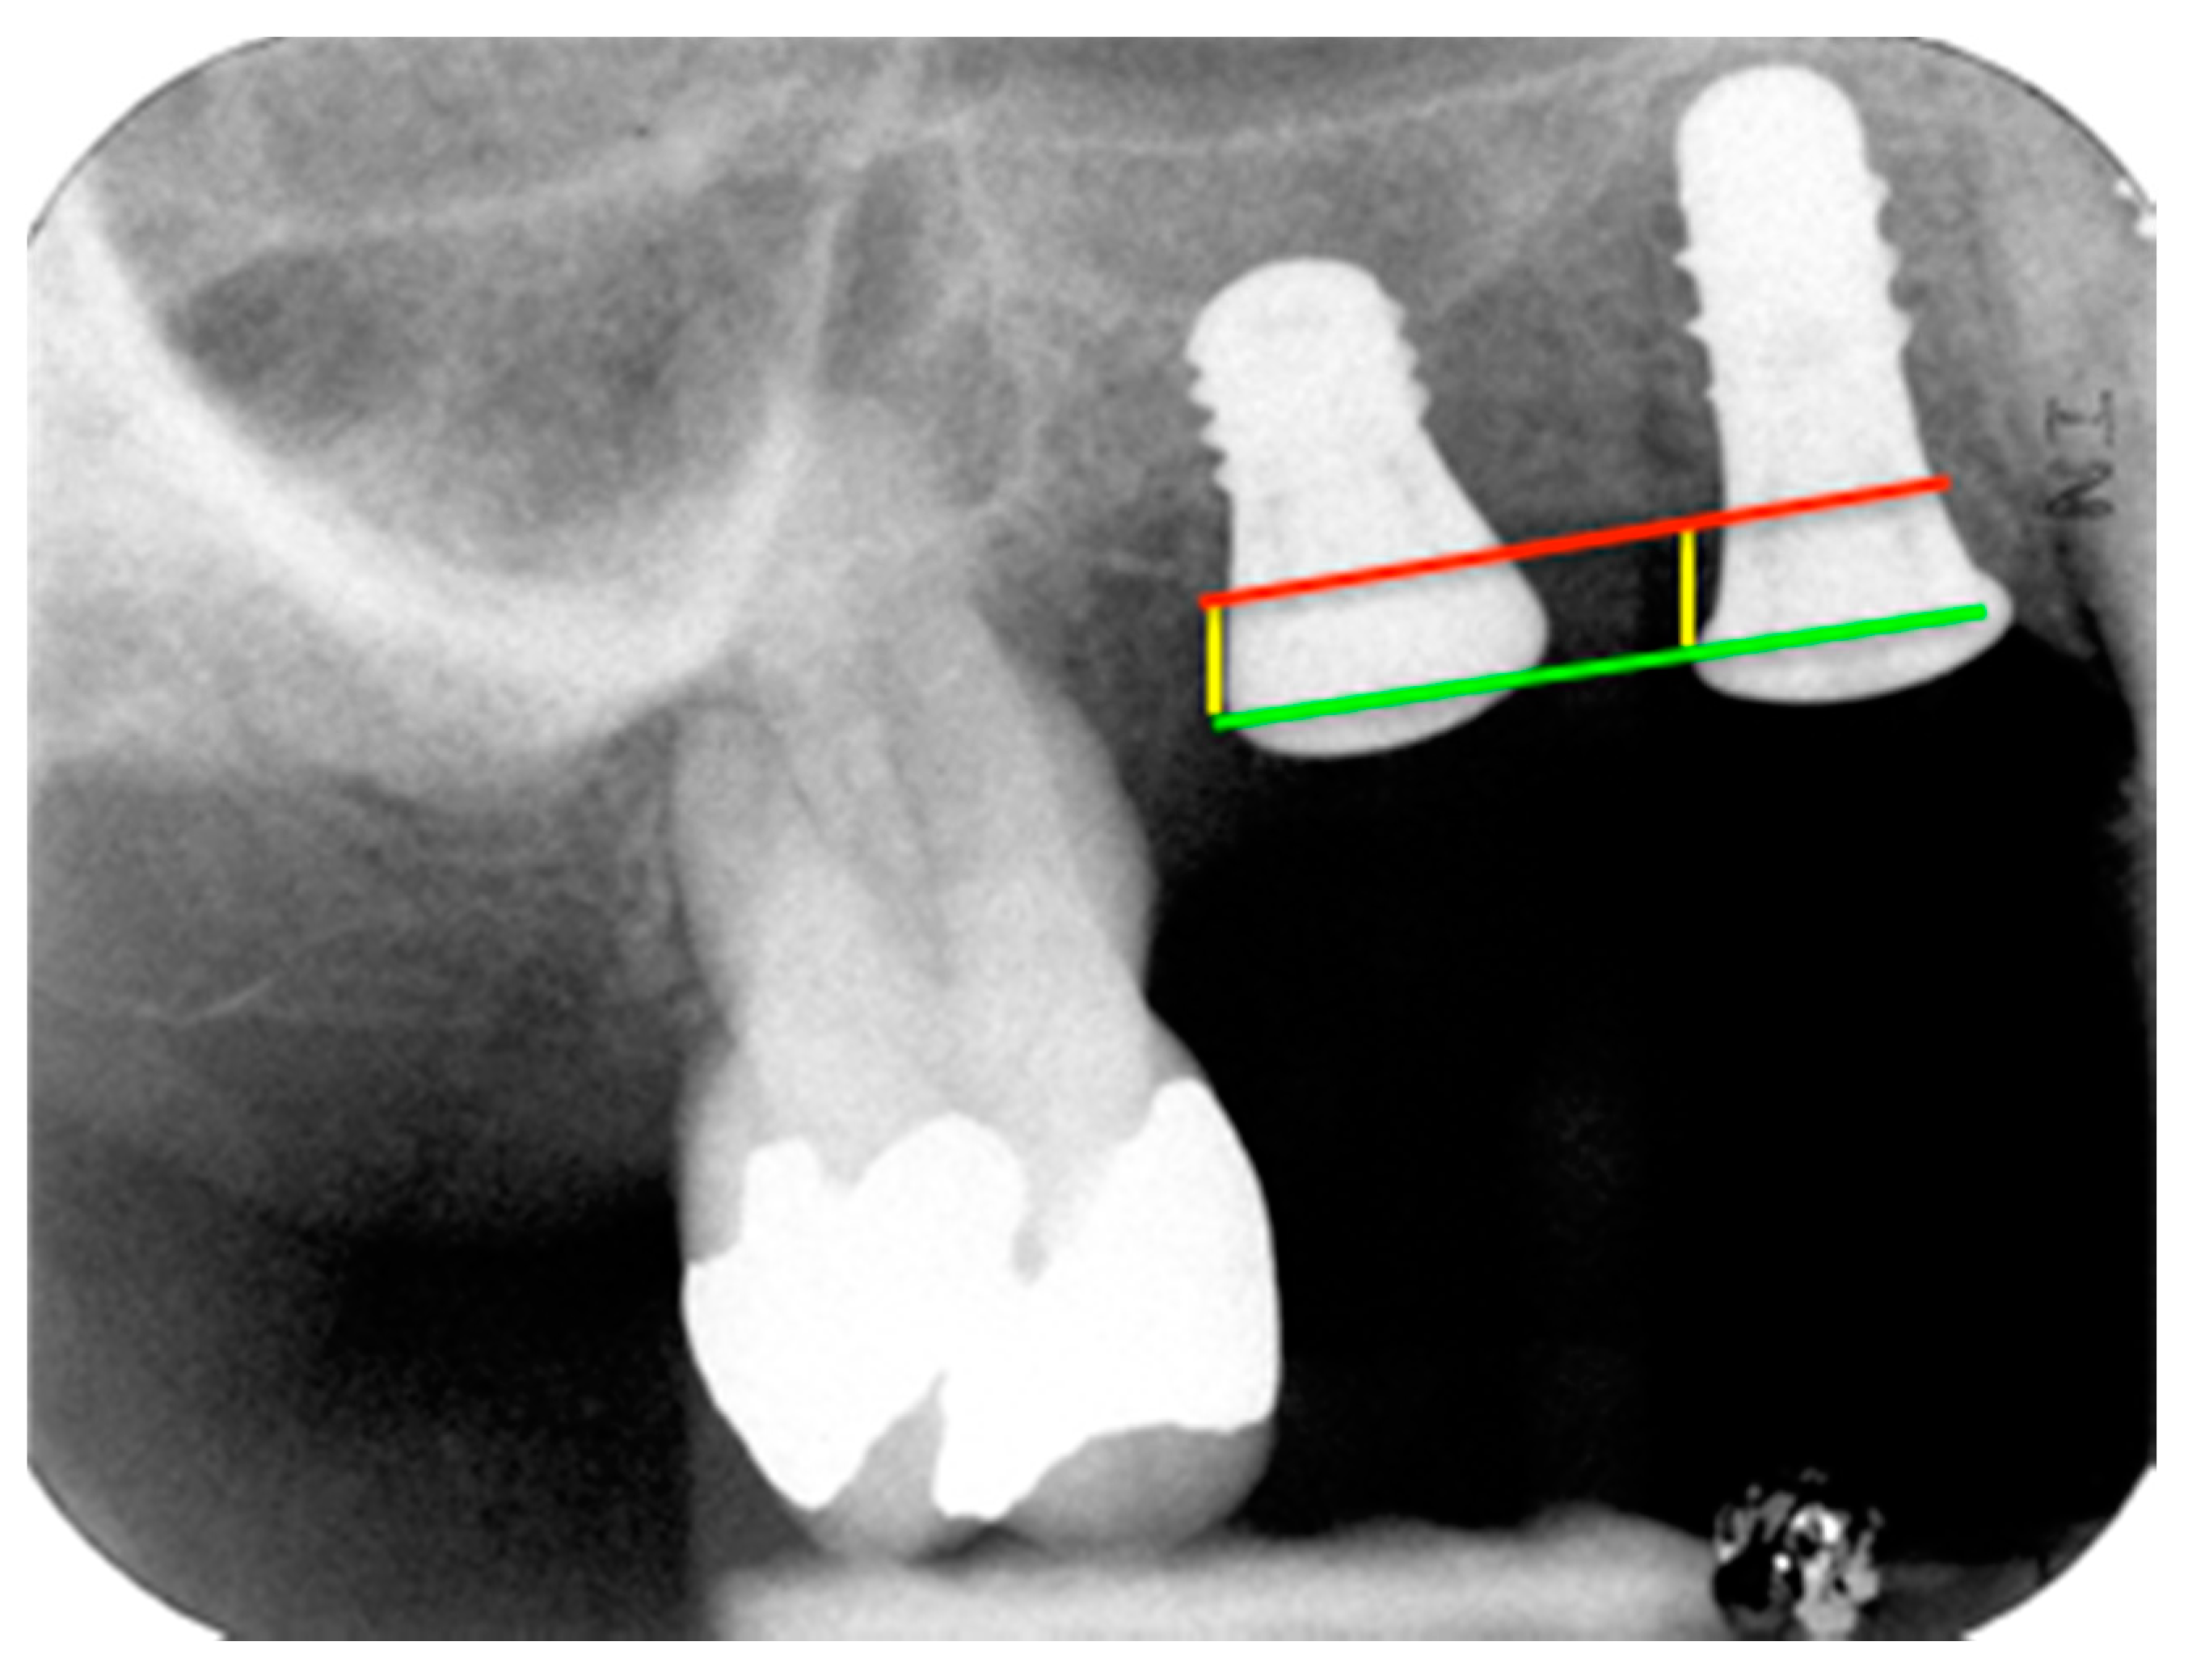

2.3. Calibration

4.1. Marginal Bone Level (MBL)

4.2. Bone tissue remodeling (MBL change)